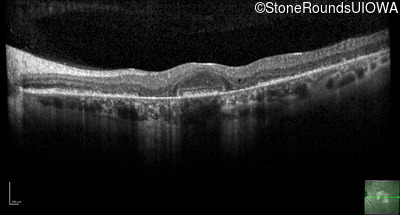

Optical Coherence Tomography - Right - 20/32 +2

Exemplar / OCT Stack